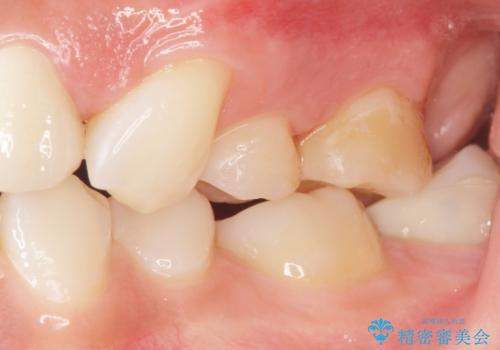

フロスを通すと臭い 歯と歯の間の虫歯 セラミックインレー 30代女性

- 歯と歯の間の虫歯治療を希望された患者様です。

フロスを通すと臭いのが気になるとの事でした。

精査したところ、左上の奥歯の間(左上56間)にう蝕を認めました。

う蝕を丁寧に除去したのち、セラミックインレーによる修復を行いました。